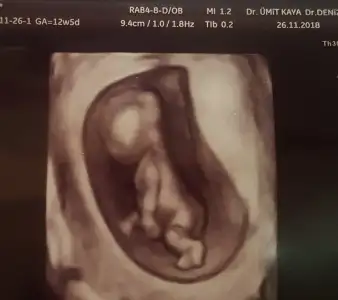

Slm bugün kontrolümüz vardı 10haftalık olmuş bebeğim 12.hafta 2li test için yeniden gidicem.bugün 2li test olur sanmıştım düşük sonrası hemen hamile kaldığımdan adet tarihi sıkıntılı ama en azından tahmini adet tarihine göre gelişim güzel ilerliyor

Resim yükledim kızlar ama ben bu usg Fotoğraflarından hiç bişi anlamıyorum başını poposunu bile ayıramıyorum ki nerde cinsiyet tahmini anlayanlardan yorum bekliyorum

Eki Görüntüle 2210747 Slm bugün kontrolümüz vardı 10haftalık olmuş bebeğim 12.hafta 2li test için yeniden gidicem.bugün 2li test olur sanmıştım düşük sonrası hemen hamile kaldığımdan adet tarihi sıkıntılı ama en azından tahmini adet tarihine göre gelişim güzel ilerliyor